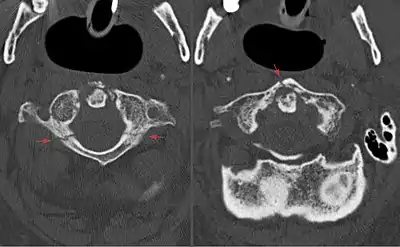

| Image of the first cervical vertebra, which is broken during a Jefferson fracture | |

A Jefferson fracture is a bone fracture of the anterior and posterior arches of the C1 vertebra,[1] though it may also appear as a three- or two-part fracture. The fracture may result from an axial load on the back of the head or hyperextension of the neck (e.g. caused by diving), causing a posterior break, and may be accompanied by a break in other parts of the cervical spine.[1]